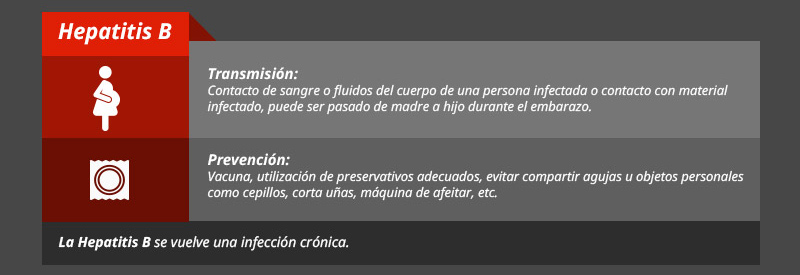

Prevención

Tipos de hepatitis